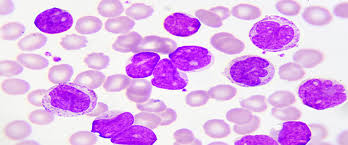

Che cos’è la leucemia acuta Le leucemie sono un gruppo eterogeneo di neoplasie che originano dalla trasformazione neoplastica di cellule emopoietiche. La cellula bersaglio della trasformazione leucemica può essere rappresentata dalla cellula staminale pluripotente...

Che cos’è l’ematopoiesi L’ematopoiesi è il processo principale che avviene nel midollo osseo. Si tratta di un processo di differenziazione progressiva di una cellula staminale “multipotente” in distinte linee: Mieloide; Eritroide; Piastrinopoietica; Linfoide. L’ematopoiesi è...